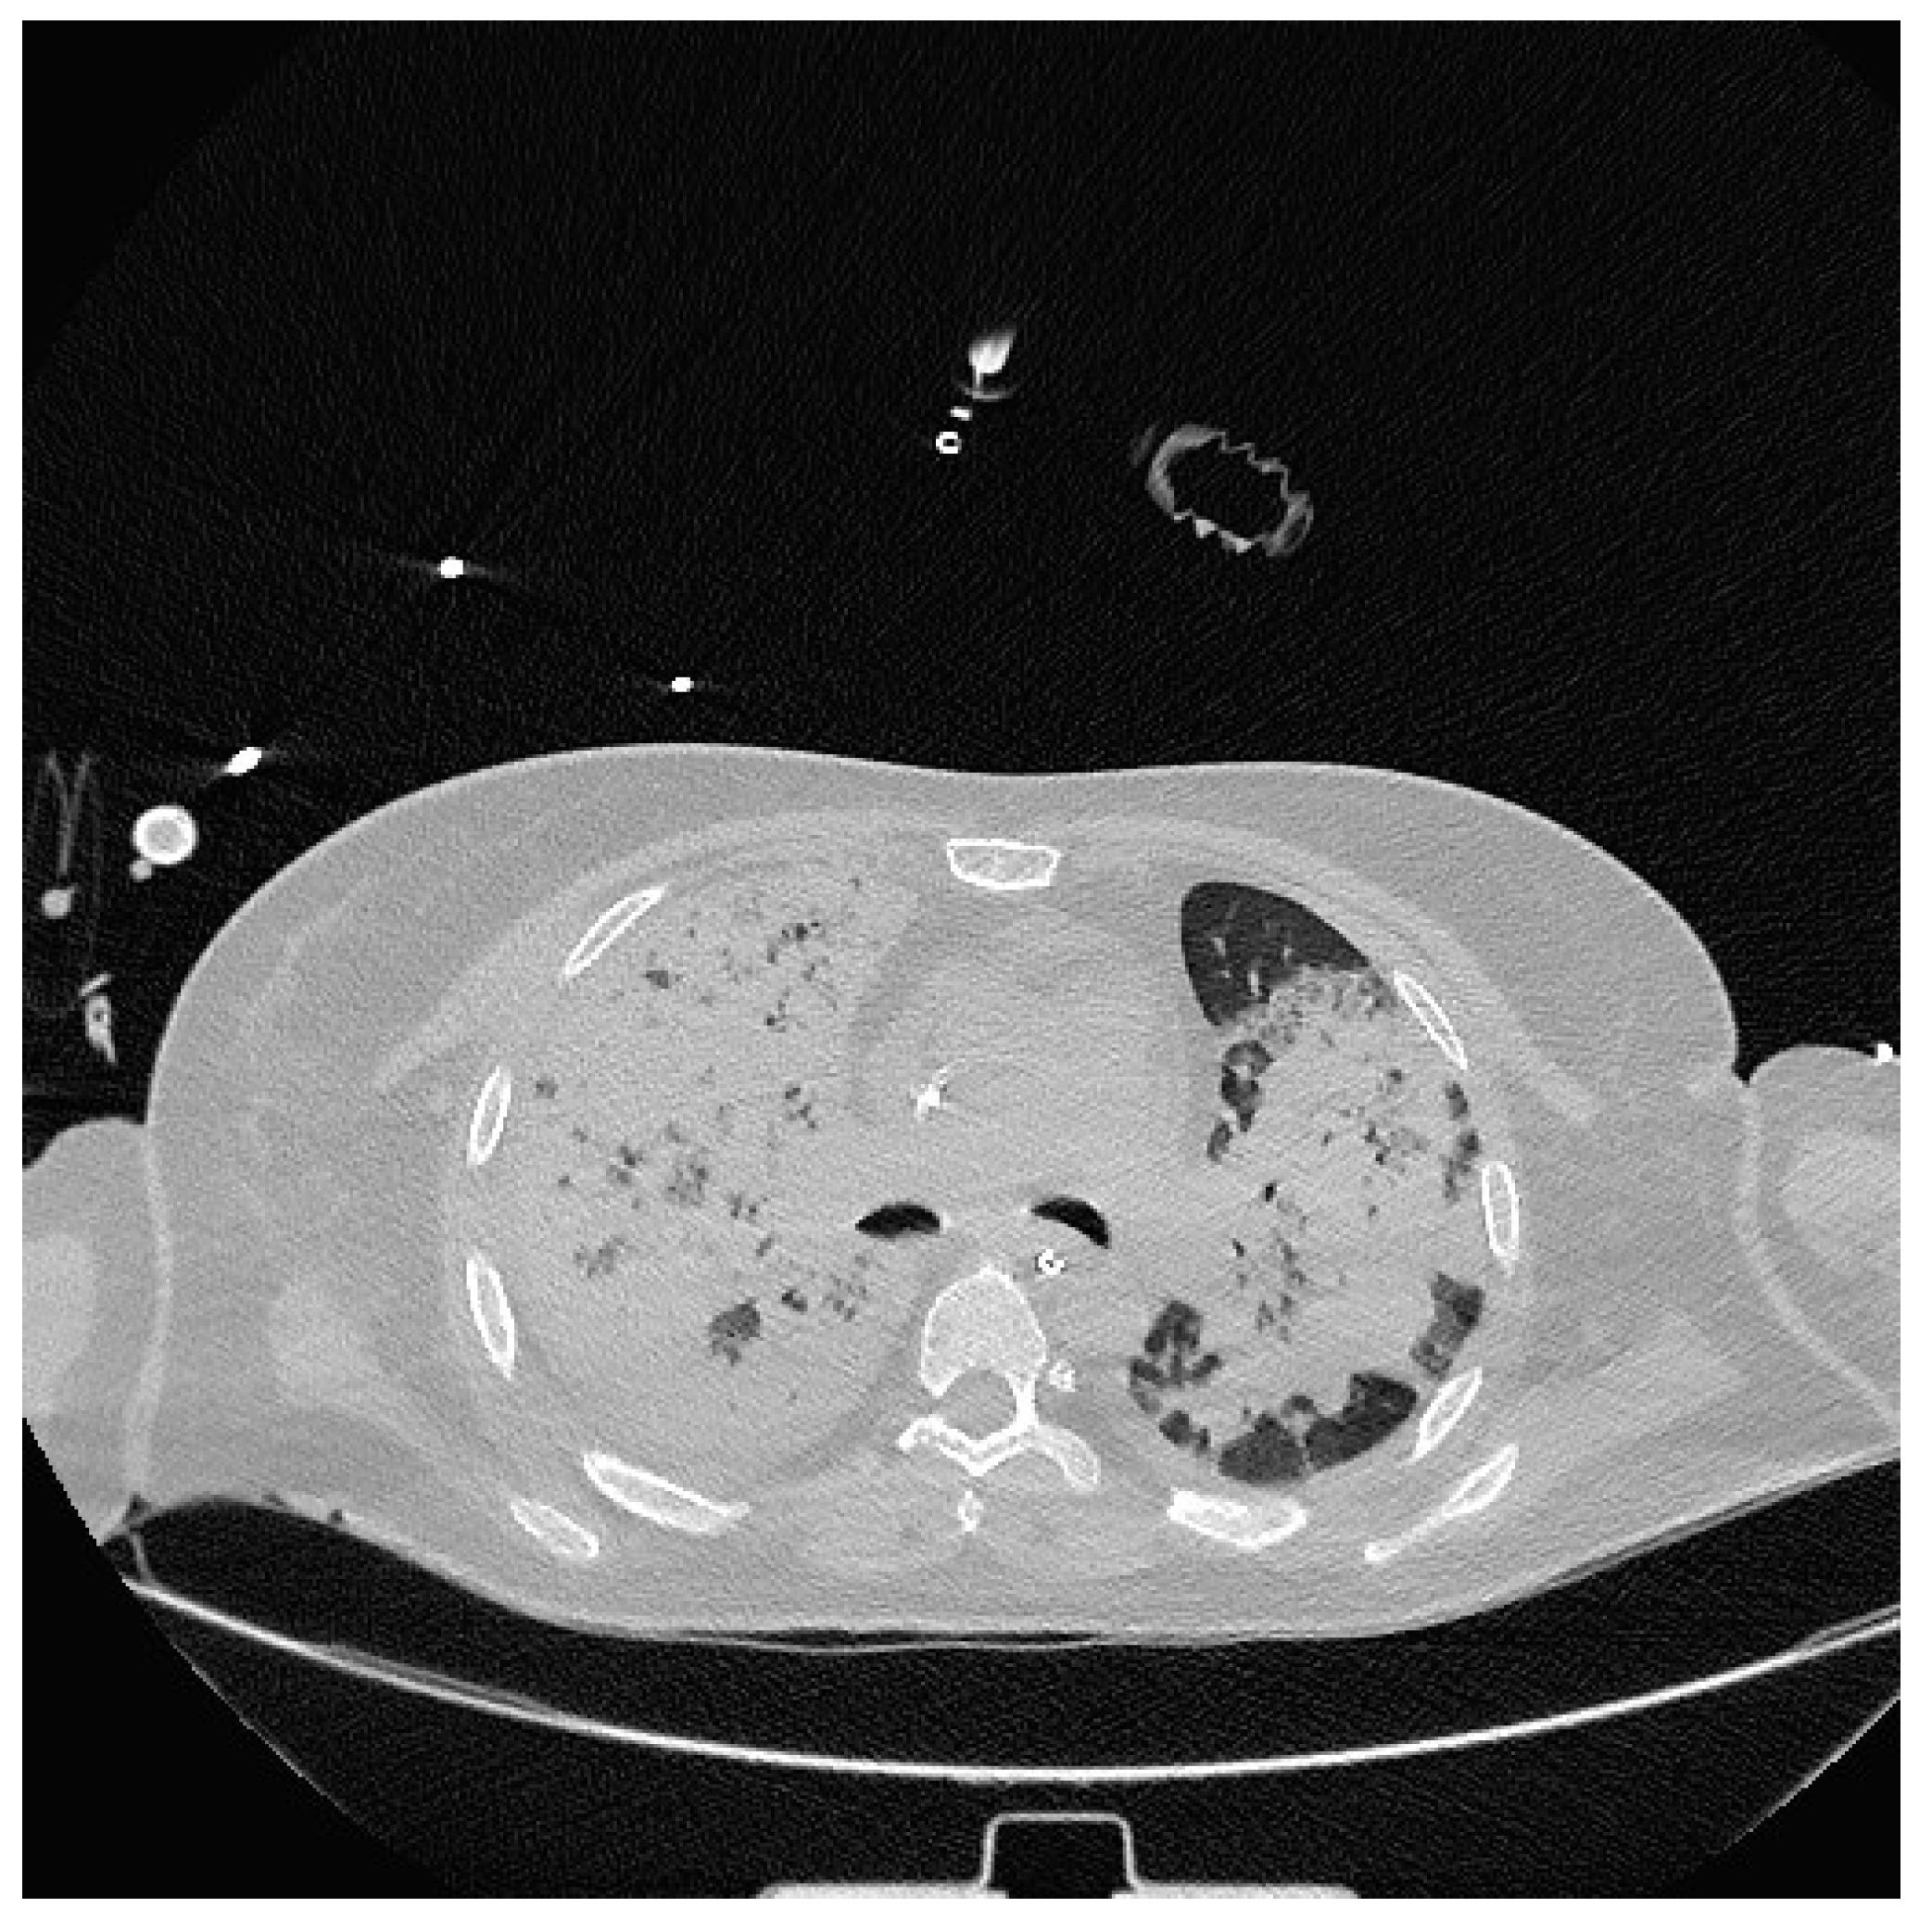

2. Case Presentation